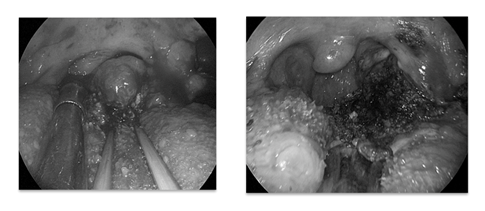

Elective local anaesthetic tracheostomy was performed for airway protection followed by removal tongue base mass via transoral endoscopic resection under general anaesthetic (Figure 4) using blade and diathermy. She had good airway post-operatively and was able to tolerate oral feeding five days after the operation. Six weeks after the operation, her tracheostomy was successfully decannulated with return of normal speech function. Histological examination concluded the mass to be a mucoepidermoid carcinoma. She was subsequently treated with chemoradiotherapy.

Figure 4 Intra-operative view for Case 2.